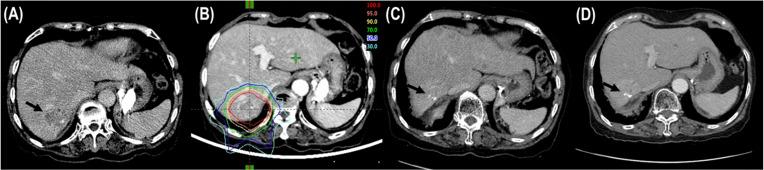

乳腺癌肝转移的大分割质子束治疗的临床疗效

Clinical Effectiveness of Hypofractionated Proton Beam Therapy for Liver Metastasis From Breast Cancer.

MATERIAL AND METHODS

Seventeen patients with LMBC treated with PBT were included in this study. The median prescribed dose of PBT was 66 GyE (range, 60-80) in 10 fractions, 5 times a week. In patients with LMBC receiving PBT, freedom from local progression (FFLP), progression-free survival (PFS), and overall survival (OS) rates were assessed.

RESULTS

The median follow-up time was 34.2 months (range, 11.5-56.1). The median FFLP time was not yet reached, and the 3-year FFLP rates were 94.1% (95% confidence interval [CI], 82.9-105.3). The median times of PFS and OS were 7.9 months (95% CI, 5.3-10.5) and 39.3 months (95% CI, 33.2-51.9), respectively, and the 3-year PFS and OS rates were 19.6% (95% CI, -1.8-41.0) and 71.7% (95% CI, 46.8-96.6), respectively. Grade 3 or higher adverse events were not observed.